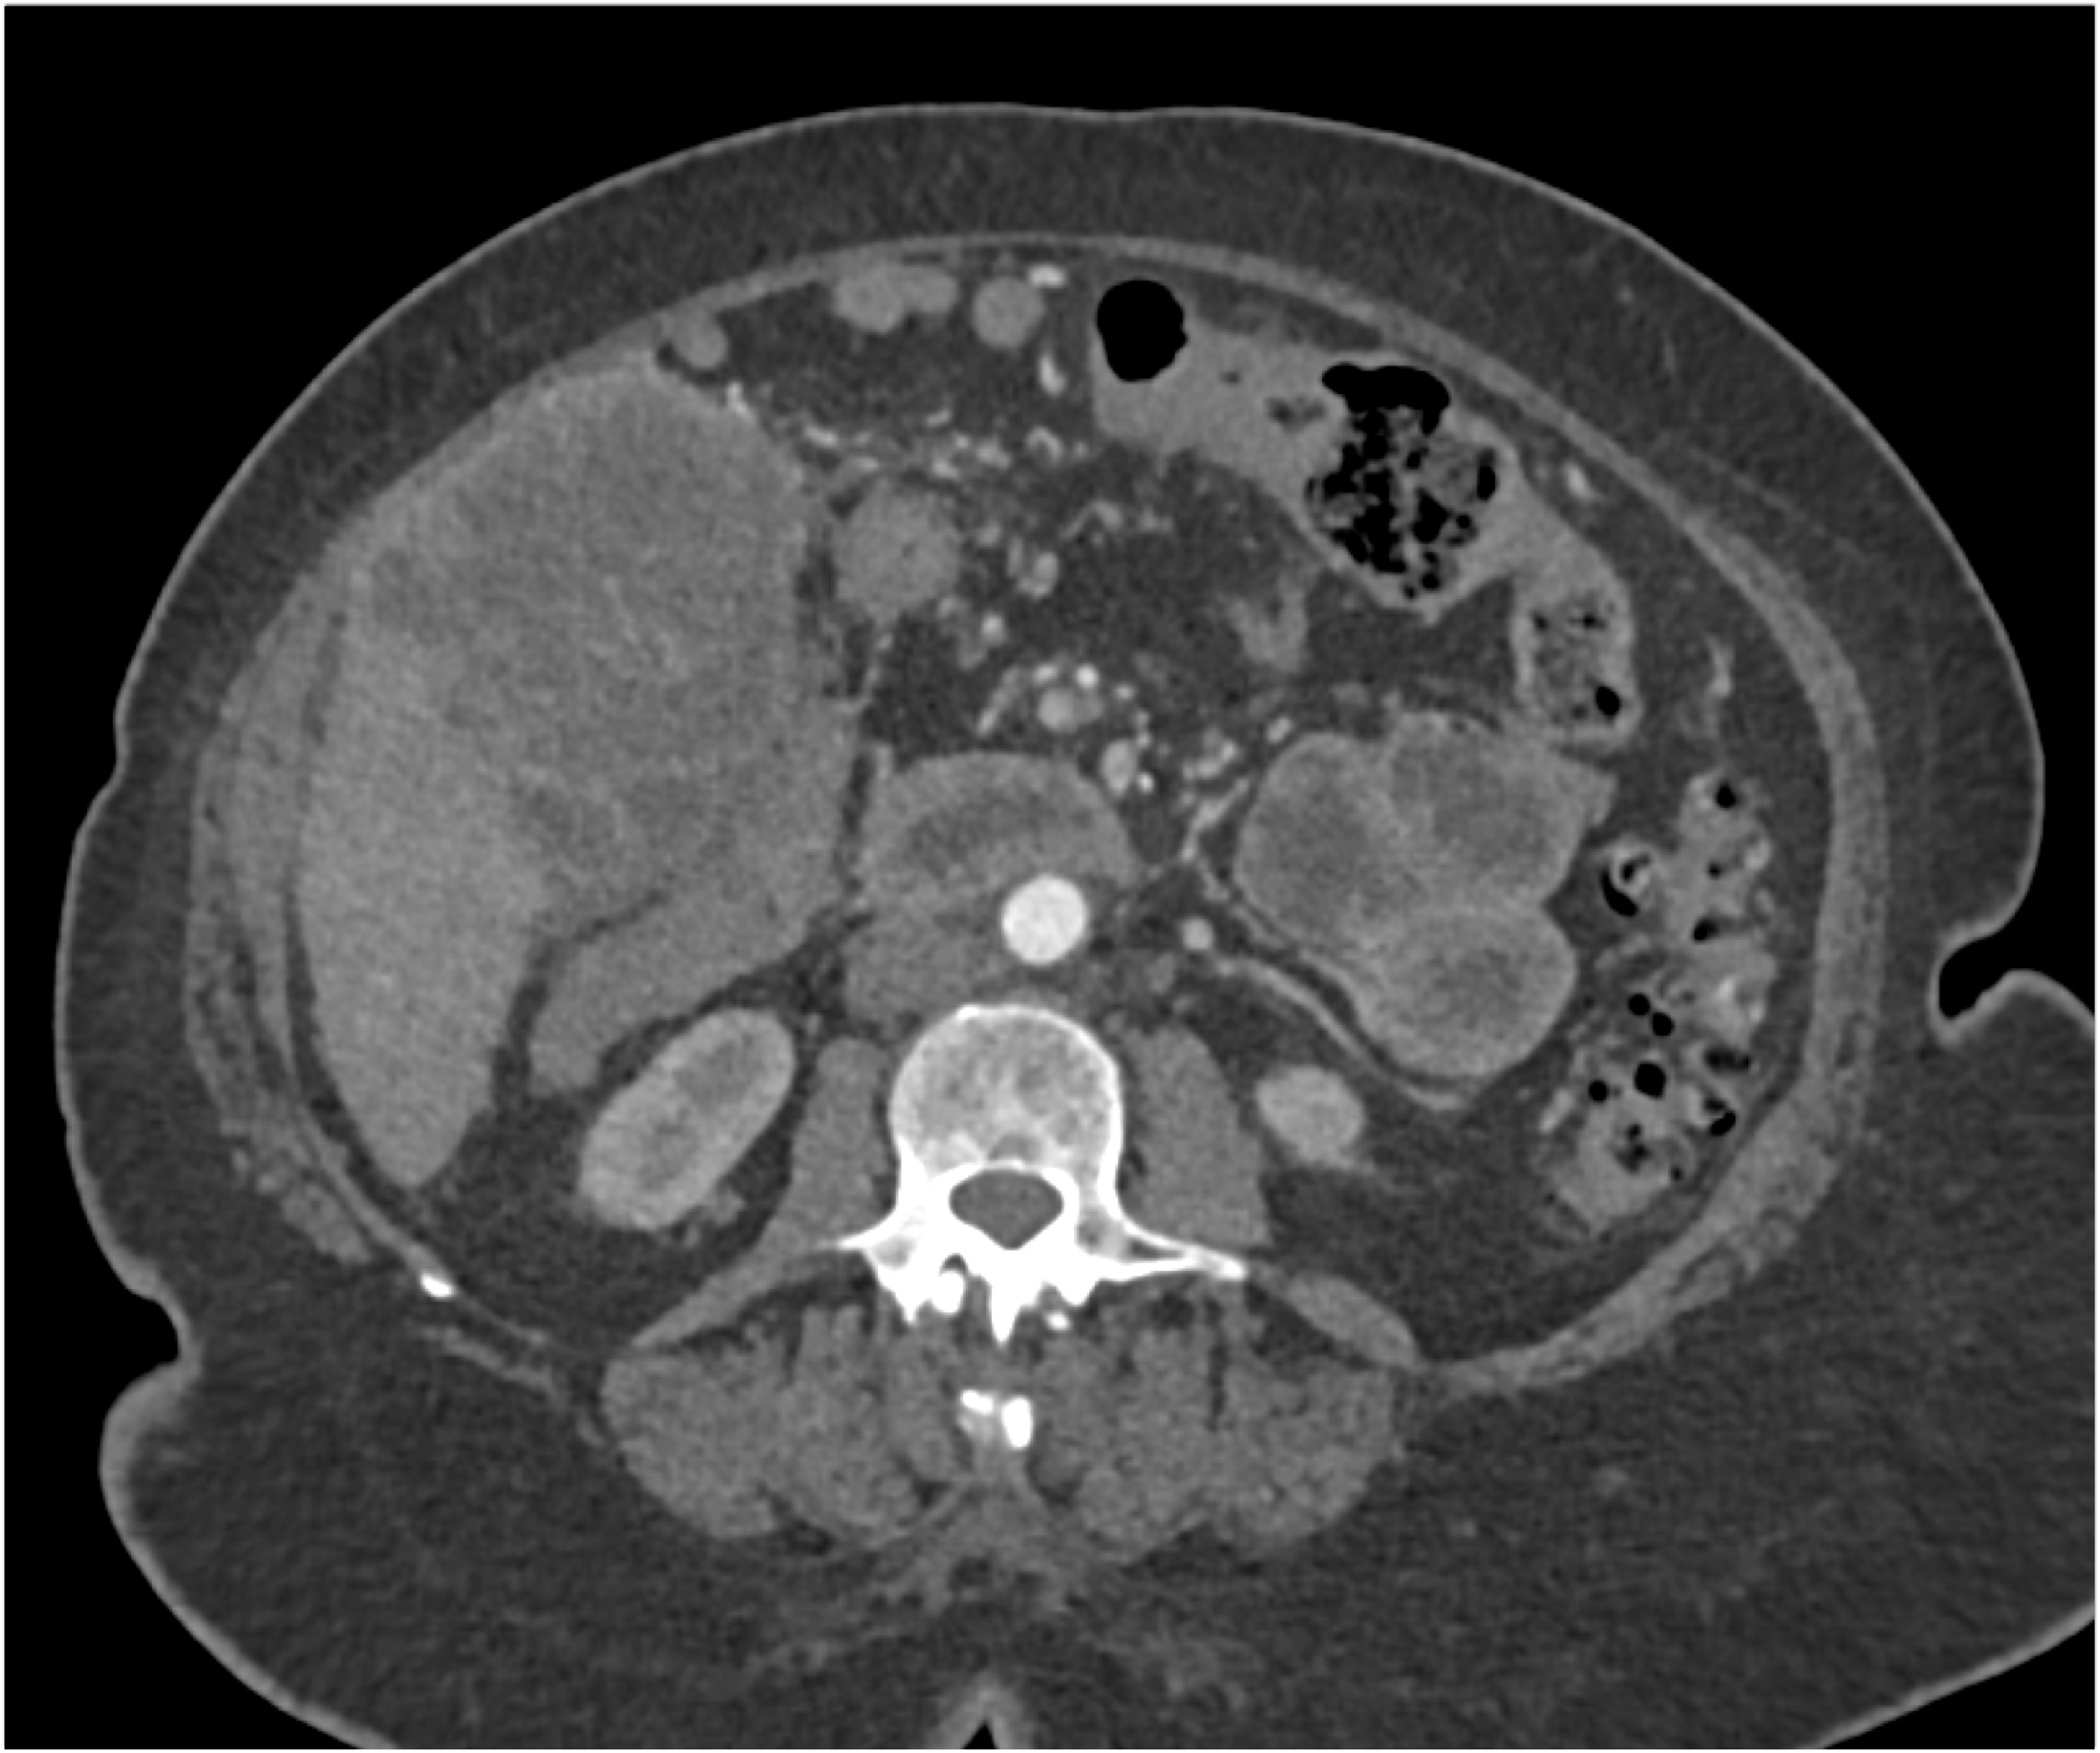

2) The differential diagnosis in this case includes?

FMD (fibromuscular dysplasia)

SAM (systemic arterial mediolysis)

Takayasu’s aortitis

all of the above